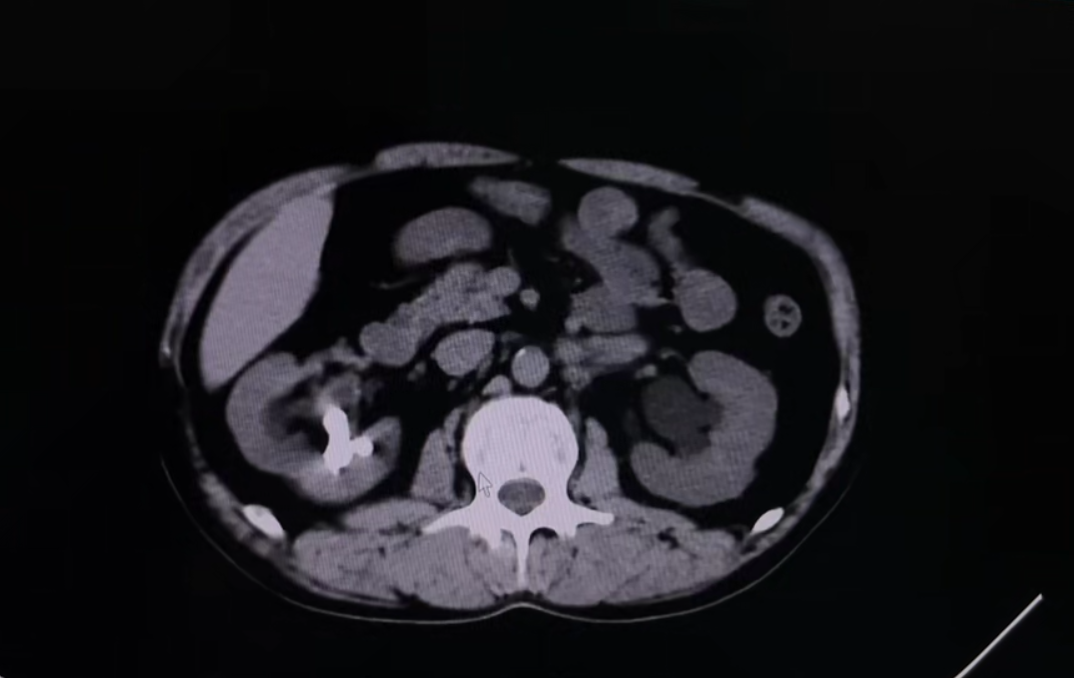

该患者因“左侧腰腹部间断性疼痛5天”入院。入院后,经过系统的泌尿系CT、超声及实验室检查,临床诊断为“双肾输尿管结石并积水和感染”。影像资料显示,其右侧肾脏结石体积较大,左侧输尿管结石已造成梗阻并引发感染,病情存在一定复杂性。